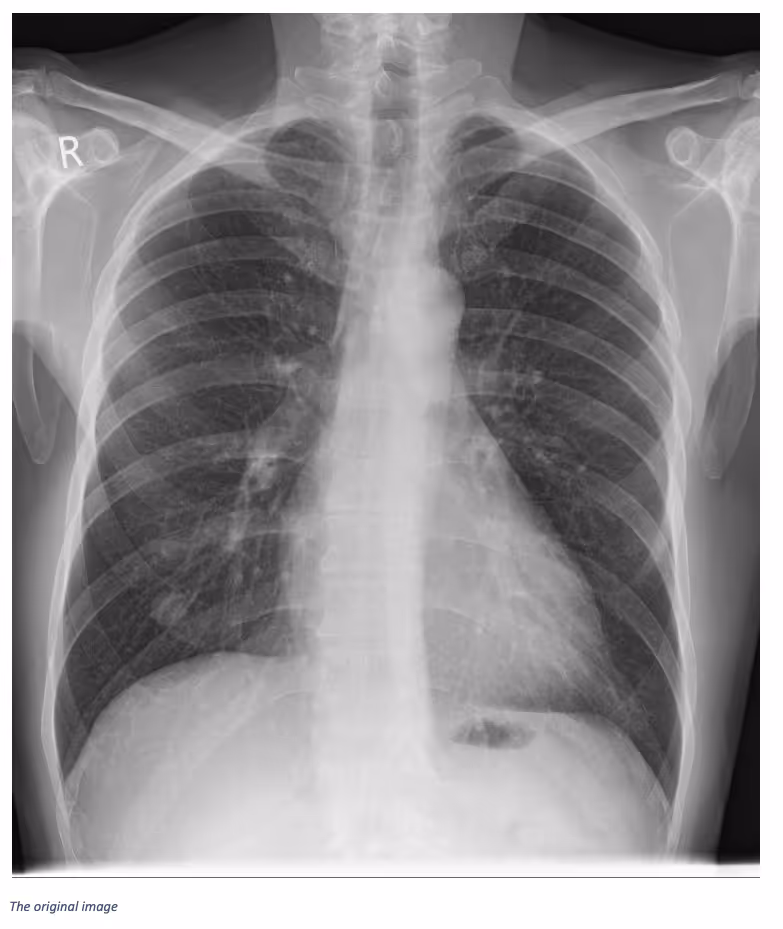

Ferrum Health partners with best-in-class AI providers offering solutions designed to reduce radiology workload and improve patient care.VinBrain Case Study: Detection of Lung Nodule in Easily Confused AreaIntroductionTypically, the structures seen in radiology studies overlap. While some abnormalities may be defined structures—such as a mass, nodule, or tumor—their appearance may not always be so well defined. As such, they may be referred to as lesions, spots, or shadows.Clinical CaseA 55-year-old male joined a chest screening program and had a Chest X-ray image. Through the image, a well-defined solitary pulmonary nodule of soft tissue density is visible in the right lower lobe. Prior examinations confirmed this as a hamartomatous mass.However, after a deep analysis, smaller, symmetrical, ill-defined nodular shadows were detected on both sides between the anterior aspect of the 5th and 6th ribs. Unlike the SPN, these shadows have an ill-defined medial border, while the lateral border is sharp.